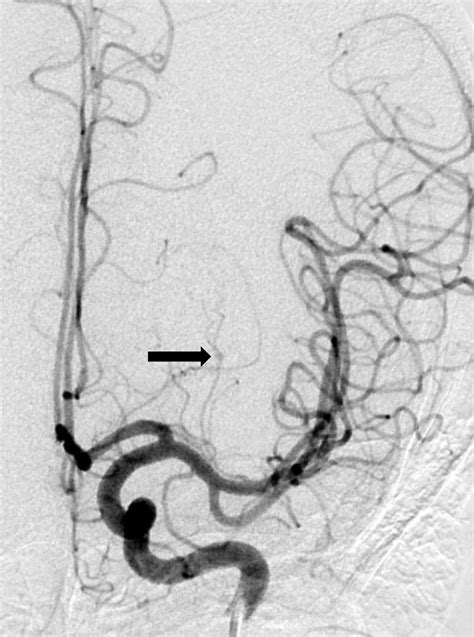

• Angiography: This procedure involves injecting a contrast dye into the blood vessels and using X-rays to visualize the blood flow. It can help identify the location and size of the aneurysm.